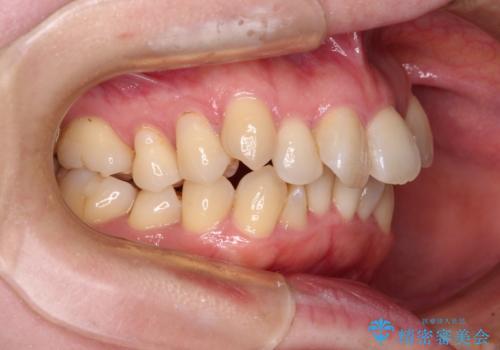

- 上下前歯のデコボコと、上顎の八重歯を気にして来院された患者様です。

下顎に対して上顎が前方にあり、第一大臼歯による咬合状態は上顎前突であったため、上顎のみ左右の第一小臼歯を抜歯し、ワイヤー装置にて矯正治療を行うこととしました。